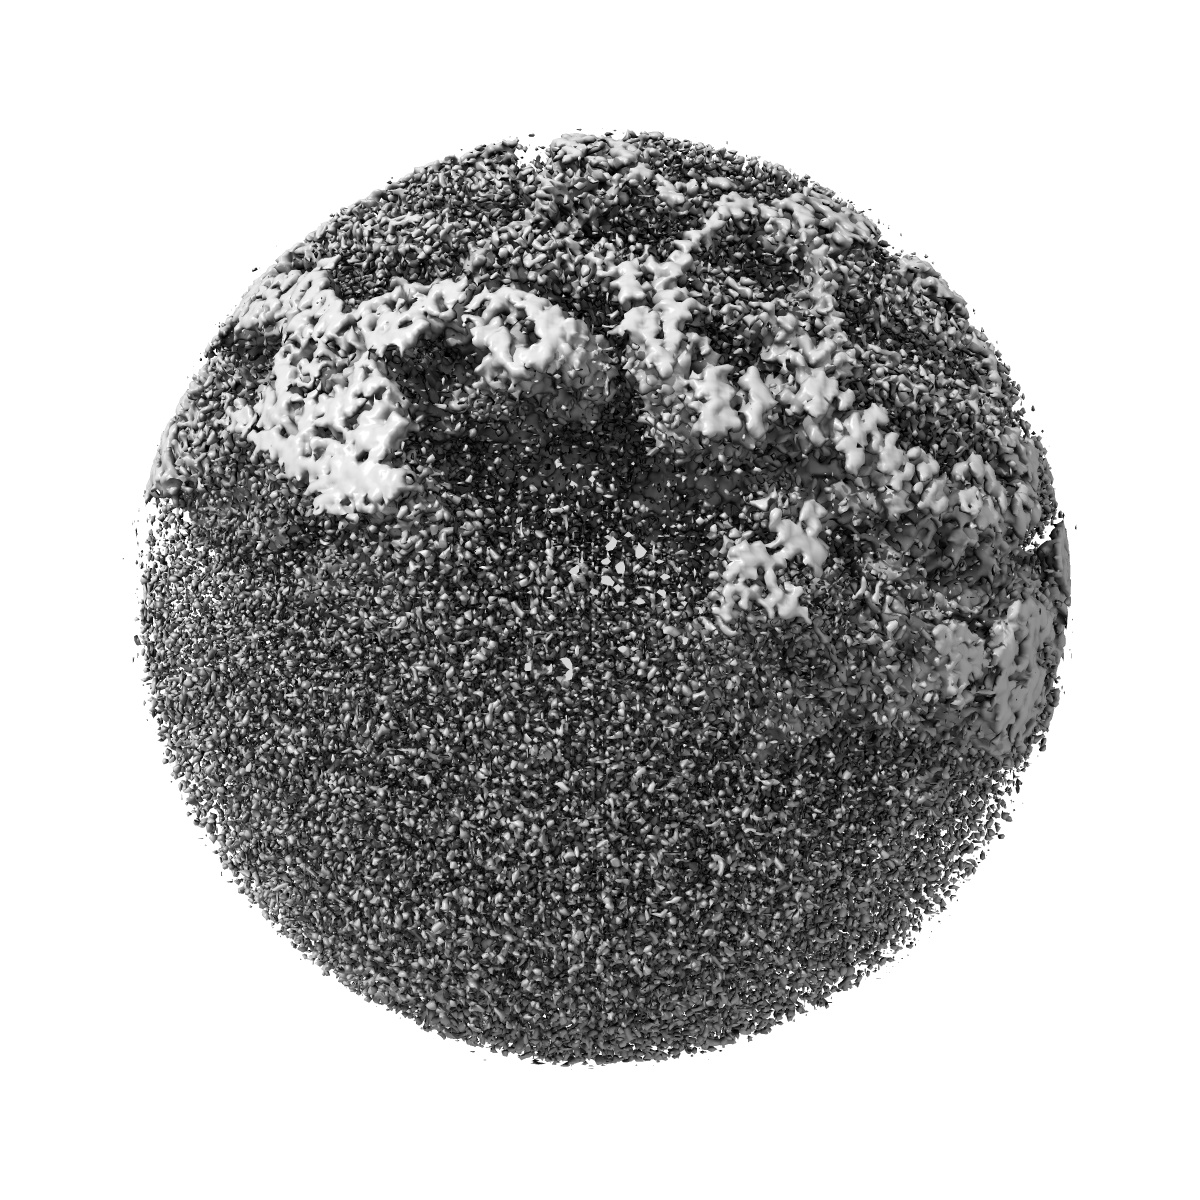

Structure of Eastern Equine Encephalitis VLP in complex with the receptor VLDLR LA3-5

Sample: East Equine Encephalitis virus VLP in complex with its receptor VLDLR LA3-5 at the asymmetric unit

The receptor VLDLR binds Eastern Equine Encephalitis virus through multiple distinct modes.

(2024) Nat Commun , 15 , 6866 - 6866